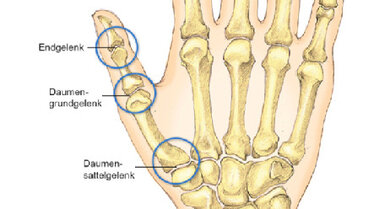

Ein Skidaumen entsteht häufig bei einem Sportunfall – wenn der Daumen "nach außen" hin stark überdehnt, also übermäßig von der Hand abgespreizt wird. Dabei reißt das innere (ulnare) Seitenband des Daumens. Dieses Band stabilisiert das Daumen-Grundgelenk auf der "Innenseite" des Daumens, also der Seite, die dem Zeigefinger benachbart ist. Nach dem Namen des verletzten Bandes heißt der Skidaumen medizinisch "Ruptur (also Riss) des ulnaren Kollateralbandes".

Hier befindet sich das Daumen-Grundgelenk sowie das Daumen-Sattelgelenk. Für die Vergrößerung auf die Lupe oben links klicken

Bei einem Skidaumen liegt ein Bänderriss (Ruptur) des inneren Seitenbandes vor, welches das Daumen-Grundgelenk (siehe Hintergrundinformation) führt. Ursache dafür ist eine starke Überdehnung des Seitenbandes nach außen, indem der Daumen beispielsweise durch einen Sturz oder direkten Ballkontakt zu stark nach außen abgespreizt wird. In Folge dieser direkten Gewalteinwirkung wird das Band deutlich überbelastet und es kann teilweise oder vollständig reißen.